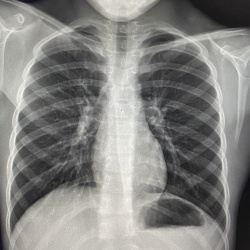

Мужчина 1981 женщина 1979гг. Оба трудятся в сфере-очень я бы сказал тесная связь с общественностью. Мужчина кондуктор автобуса,женщина полы моет в школе. Случаи свежие(мед.осмотры с начала года)....